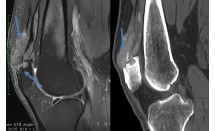

La maladie de Paget, ou ostéïte déformante, est une maladie du tissu osseux caractérisée par des phases successives de destruction et de reconstruction osseuse aboutissant aux anomalies décrites sur la figure 1.